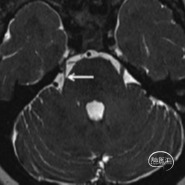

MRI所见三叉神经脑池段

MRI轴位所见麦氏囊